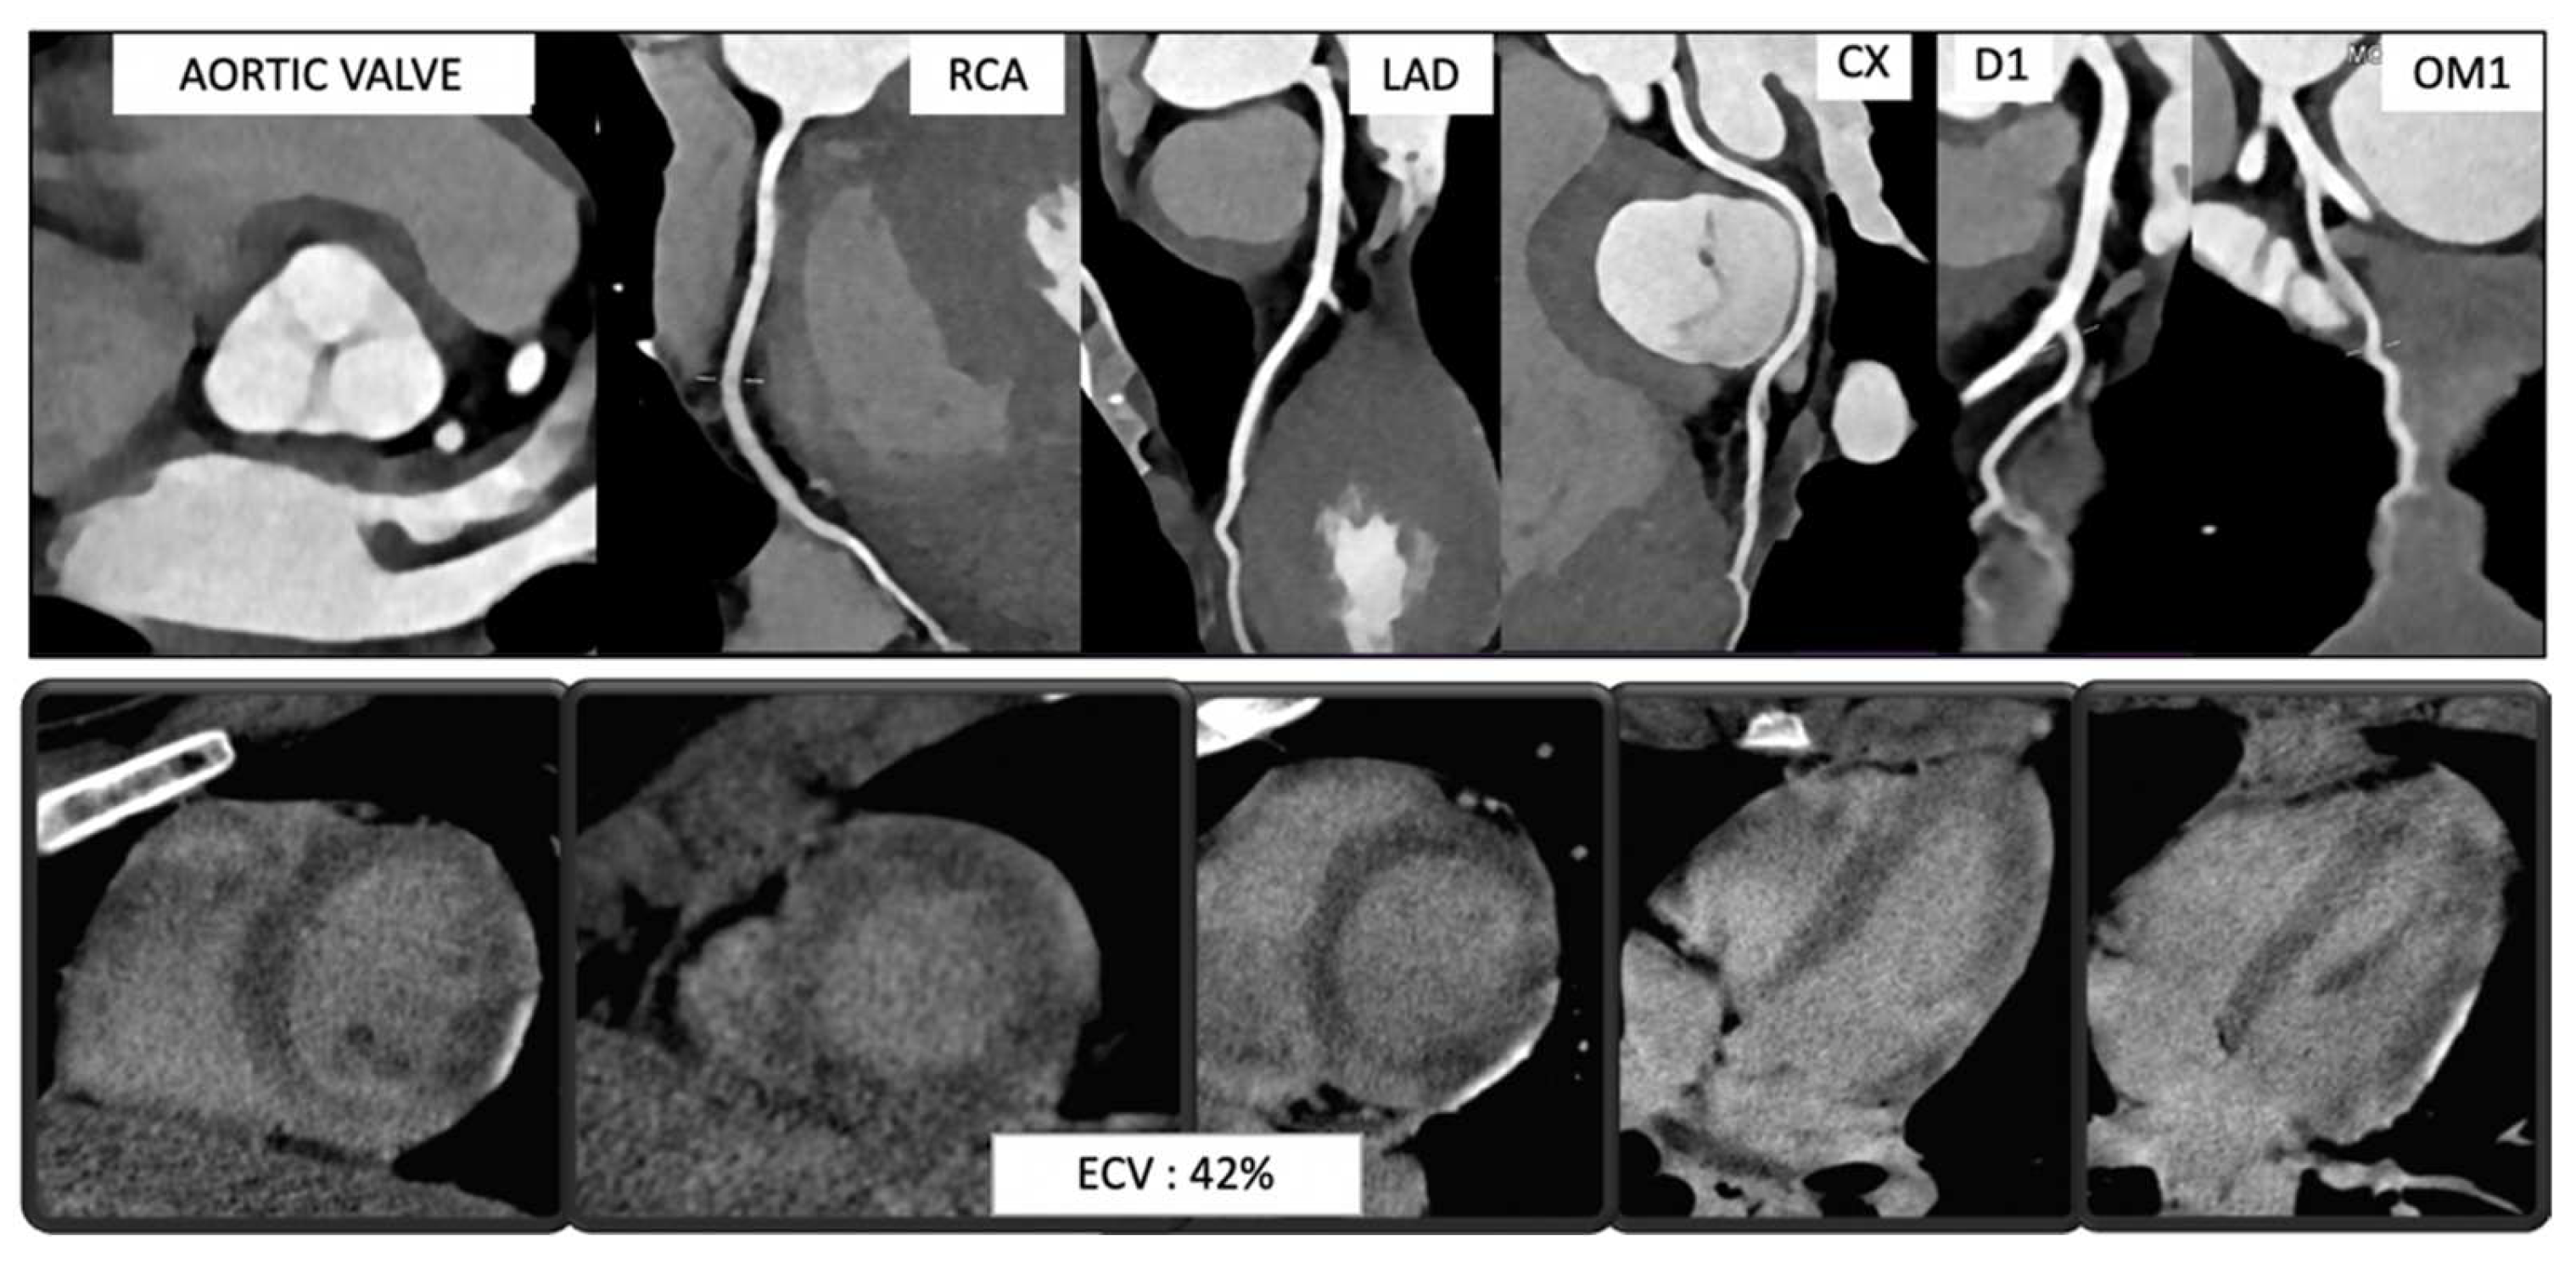

- Albrecht, M.H.; De Cecco, C.N.; Schoepf, U.J.; Spandorfer, A.; Eid, M.; De Santis, D.; Varga-Szemes, A.; van Assen, M.; von Knebel-Doeberitz, P.L.; Tesche, C.; et al. Dual-Energy CT of the Heart Current and Future Status. Eur. J. Radiol. 2018, 105, 110–118. [Google Scholar] [CrossRef]

- Chellini, D.; Kinman, K. Dual-Energy CT Principles and Applications. Radiol. Technol. 2020, 91, 561CT–576CT. [Google Scholar]

- Tarkowski, P.; Czekajska-Chehab, E. Dual-Energy Heart CT: Beyond Better Angiography-Review. J. Clin. Med. 2021, 10, 5193. [Google Scholar] [CrossRef]

- Dell’Aversana, S.; Ascione, R.; De Giorgi, M.; De Lucia, D.R.; Cuocolo, R.; Boccalatte, M.; Sibilio, G.; Napolitano, G.; Muscogiuri, G.; Sironi, S.; et al. Dual-Energy CT of the Heart: A Review. J. Imaging 2022, 8, 236. [Google Scholar] [CrossRef]

- Schwarz, F.; Ruzsics, B.; Schoepf, U.J.; Bastarrika, G.; Chiaramida, S.A.; Abro, J.A.; Brothers, R.L.; Vogt, S.; Schmidt, B.; Costello, P.; et al. Dual-Energy CT of the Heart--Principles and Protocols. Eur. J. Radiol. 2008, 68, 423–433. [Google Scholar] [CrossRef]

- Miller, C.A.; Naish, J.H.; Bishop, P.; Coutts, G.; Clark, D.; Zhao, S.; Ray, S.G.; Yonan, N.; Williams, S.G.; Flett, A.S.; et al. Comprehensive Validation of Cardiovascular Magnetic Resonance Techniques for the Assessment of Myocardial Extracellular Volume. Circ. Cardiovasc. Imaging 2013, 6, 373–383. [Google Scholar] [CrossRef]

- Lee, H.-J.; Im, D.J.; Youn, J.-C.; Chang, S.; Suh, Y.J.; Hong, Y.J.; Kim, Y.J.; Hur, J.; Choi, B.W. Myocardial Extracellular Volume Fraction with Dual-Energy Equilibrium Contrast-Enhanced Cardiac CT in Nonischemic Cardiomyopathy: A Prospective Comparison with Cardiac MR Imaging. Radiology 2016, 280, 49–57. [Google Scholar] [CrossRef]